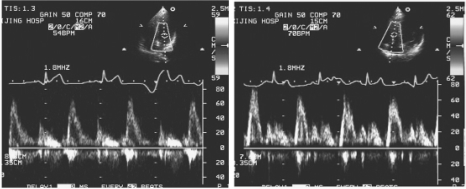

2.频谱特点 正常心脏各部位频谱特点及时相不同,见表10-7。正常房室瓣(图10-32)及半月瓣血流频谱见图10-33。

图10-32 左图:二尖瓣下正常血流频谱图;右图:三尖瓣下正常血流频谱图